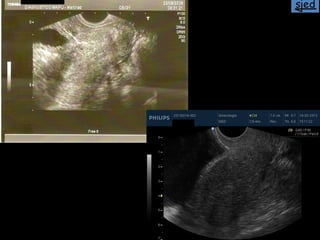

La ecografía ginecológica transrrectal es una ecografía endocavitaria que usa la vía transrrectal en lugar de la transvaginal. Se indica principalmente para pacientes vírgenes con ecografías ginecológicas no concluyentes, pacientes con vaginismo severo o hipotrofia marcada del introito y vagina. La técnica es similar a la ecografía transvaginal pero sin el tope vaginal, y permite imágenes casi idénticas.